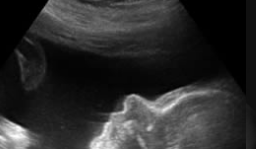

• Ecografía